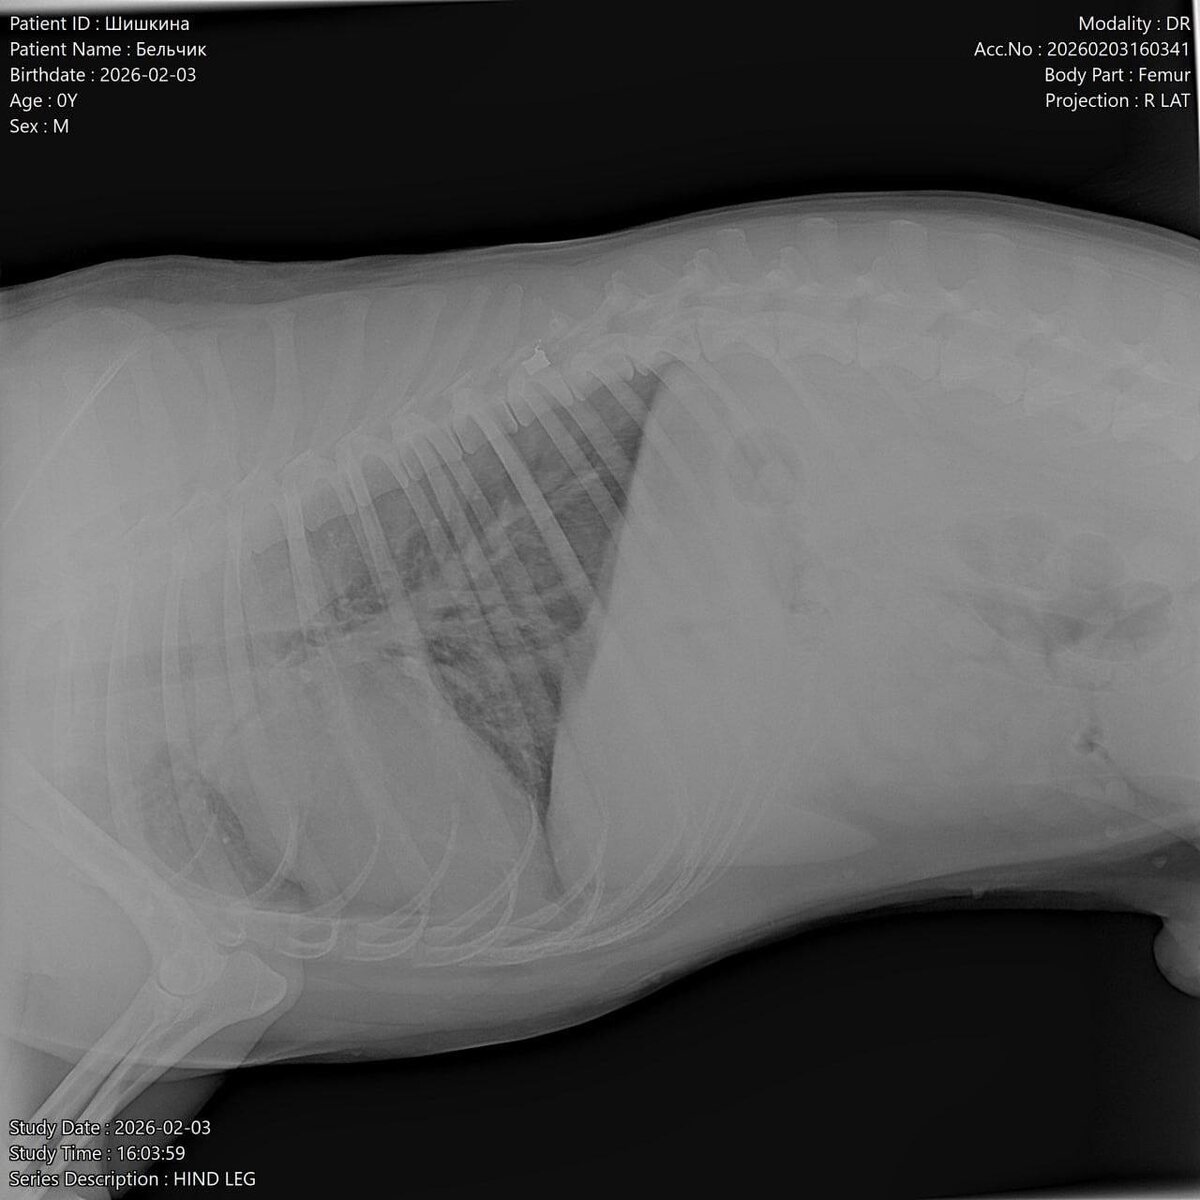

В клинике врачи сообщили шокирующие новости — в пса стреляли. По рентгену у него пуля в позвоночнике и перелом таза.

Как сообщили порталу @donday.ru в приюте «Феникс» города Азов, пса нашли днем 3 февраля в микрорайоне Мичуринец-3.

Пес метис (лайка и хаски) вышел к людям на трассу возле кафе. Изначально все думали, что травмы собака получила после ДТП.

Но потом обнаружили, что собака не может встать на задние лапы, тянет их за собой, - уточнили в приюте.